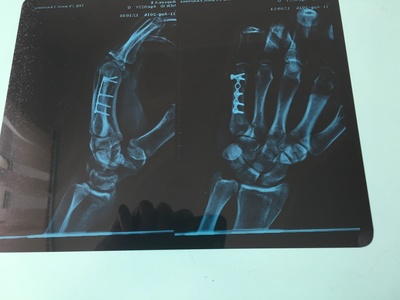

Для восстановлении верхних конечностей разработано большое количество имплантов. Микропластины предназначены для пальцев. При травмированных ладонях пластины устанавливаются исключительно с тыльной стороны, что позволяет избежать повреждения многочисленных нервов, сосудов, сухожилий.

по снимку не видно, насколько хорошо можно репонировань (сопоставить) отломки без разреза. Если можно - то спица, она ставится через прокол. Если надо резать - то пластина.

Это классический перелом боксера. Ставьте спицу.

в данной ситуации необходимо ставить спицы(4 недели ходить со спицами и 4 недели с гипсом) + перевязки. Спицы и гипс не мочить!!

Очень советую спицы. Их вытащат через полтора месяца, пластину - через год-полтора. Но это не самое стрёмное соображение. Самое стрёмное в пластине то, что под неё нужно делать невъебический (по сравнению со спицами) доступ. э-э-э, разрез. А на кисти очень нежные сухожилия и мышцы. Ну и вообще нынче все вмешательства оперативные стараются делать максимально малоинвазивными.

Врач дал выбор(мол думай, пока отёк спадает) - спицы или пластина. мол сам выбирай. Я нихера не смыслю в этом

Был перелом похожий несколько лет назад. Тогда выбрал спицы. Срослось все нормально, сейчас бегаю, прыгаю, баб е. ну в общем не жалуюсь, единтсвенное, иногда палец больной дергается после длительных тренировок но мне кажется это от самого перелома уже, а так норм. Спицы были бесплатны и сейчас, а пластины были за деньги и не понятно когда. Я хотел поскорее все закончить, выбрал спицы. В вашем случае рекомендую слушать хирурга который будет вас оперировать, ибо ему с этим работать и ему виднее. На счет вытаскивать, спицы вытащили через 1,5 месяца после операции, потом еще пол месяца в гипсе и свободен, на счет пластин не знаю, их вообще можно не вытаскивать. Повторюсь, слушайтесь своего хирурга.